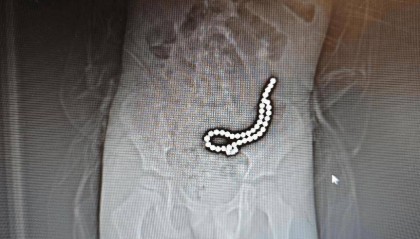

整整37颗!云南4岁孩子身体里取出……医生紧急提醒!

磁力珠色彩绚丽、玩法多样,深受小朋友喜爱。但如果误食,后果却会很严重。 近日,丽江市人民医院接收了一...

欧意交易所最新app下载 2025-06-17 68